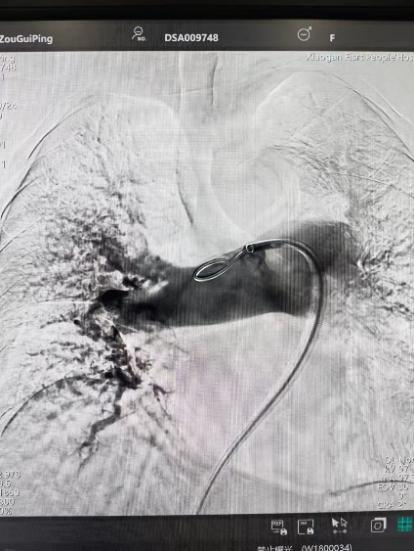

術(shù)前

手術(shù)在局部麻醉下進行,團隊通過股靜脈穿刺,將專用抽栓導管精準送達肺動脈栓塞部位,利用負壓抽吸技術(shù)成功清除大量血栓;隨后,在血栓局部精準灌注溶栓藥物,進一步溶解殘余血栓,恢復肺部血流灌注;同時,為防止下肢深靜脈血栓再次脫落引發(fā)肺栓塞,團隊為患者置入下腔靜脈濾器,整個手術(shù)歷時約1小時。術(shù)后,鄒婆婆呼吸困難癥狀即刻得到緩解,血氧飽和度顯著提升,右心負荷明顯減輕,目前身體狀況正在逐步恢復中。